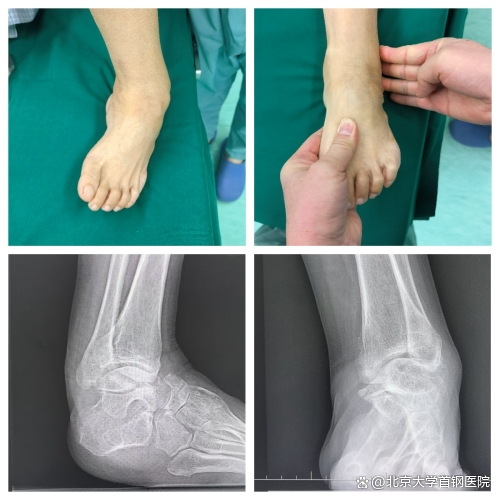

“小时候只是有点内翻,没当回事,没想到越长大越严重。”李女士的声音带着无奈,“后来走路都得拄拐,稍微走几步就疼得钻心,现在只能靠轮椅出门。” 随着年龄增长,足部畸形如同藤蔓般生长,一点点侵蚀着她正常行走的权利,将她的生活圈越缩越小。接诊的副主任医师王占国深知,这绝非普通的足部畸形。经过细致查体,真相浮出水面:李女士患的是腓骨肌萎缩症引发的重度马蹄高弓内翻足,距骨扁平、跟骨短宽,踝关节诸骨的解剖关系早已错乱,多处筋膜和韧带挛缩如紧绷的琴弦,关节退变引发的重度关节炎更是让治疗难上加难。

“先天性马蹄内翻足最佳治疗窗口是出生后5—7天,9月龄前干预效果最好。”王占国解释道,“但李女士错过了黄金期,畸形已伴随数十年,软组织和骨骼结构都发生了不可逆的改变,保守治疗收效甚微,只有手术才能为她‘扶正’脚下之路。”这个结论,既坚定了治疗方向,也意味着一场硬仗即将打响。